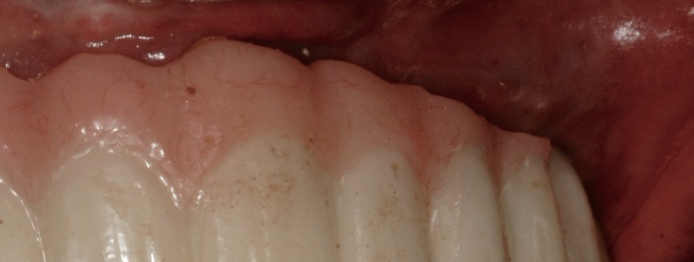

There are a wide variety of such interdental products on the market. For implant patients, the author recommends choosing an oral irrigator that pulsates and has at least two tips: the universal tip and the dental implant tip with three tufts. A Tufts University School of Dental Medicine study found a water flosser with implant tip was 145% more effective than string floss around implants when used in conjunction with a manual toothbrush.9 Significant reduction of gingival bleeding at 2 weeks and 30 days, respectively, were reported.9 Improvement in the health of tissues around implants can be seen in one patient who presented with inflammation around an implant (Figure 1), and another patient with a full-arch prosthesis that now has minimal-to-no plaque around both the top and bottom peri-implant tissues (Figure 2).

Full-arch prosthesis showing minimal-to-no plaque around both the top and bottom peri-implant tissues after oral irrigator use.

Figure 2